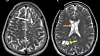

Leger trodde først det var medtfødte cyster i hjernen som forårsaket smertene. Det var feil.

Legene mistenkte at det var medfødte cyster som sto bak de store smertene mannen led av.

Det var det ikke.

Ved nærmere undersøkelser ble det klart mannen hadde bendelormegg i hjernen. Eggene hadde kapslet seg inn, og det var disse som ga mannen de store smertene i hodet, skriver Din Side.